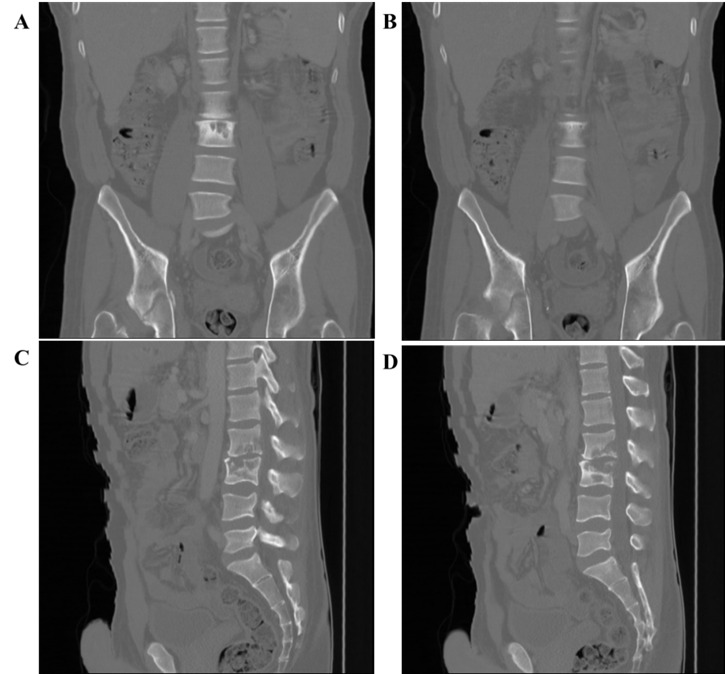

在这个临床案例中,一名男子的优势侧腹股沟受伤,他显然是在前一天的足球训练中受伤的。这名男子无法在无人帮助的情况下行走,只能用轮椅运送。咨询医生在发现很少的临床证据,X光片上也没有任何明显的迹象表明严重急性损伤后,开始怀疑。随后的详细检查显示,肌肉骨骼(MSK)和泌尿生殖道(GUT)系统的肺外结核(EPTB),并伴有病理性髋臼骨折,是腹股沟损伤的原因。EPTB的治疗解决了这种情况,尽管免疫功能低下,但在五年后没有复发,也没有长期后遗症。我们介绍了临床病例和五年的随访。该病例提醒人们,其他情况可能会模仿运动损伤,并进一步说明了这种情况的罕见表现。

In this clinical case, a man presented with a groin injury on his dominant side, which he apparently sustained in football (soccer) practice on the previous day. The man was unable to walk unassisted and had to be transported in a wheelchair. The consulting practitioner grew suspicious upon finding minimal clinical evidence and nothing notable on the X-ray to suggest a severe acute injury. A subsequent detailed workup revealed extrapulmonary tuberculosis (EPTB) of the musculoskeletal (MSK) and genitourinary tract (GUT) systems, complicated by a pathological fracture of the acetabulum, as the cause of the groin injury. Management of the EPTB resolved the condition with no relapse nor long-term sequelae beyond five years, despite being immunocompromised. We present the clinical case and a five year follow-up. The case serves as a reminder of the possibility that other conditions may mimic sports injuries and further illustrates a rare presentation of such a condition.